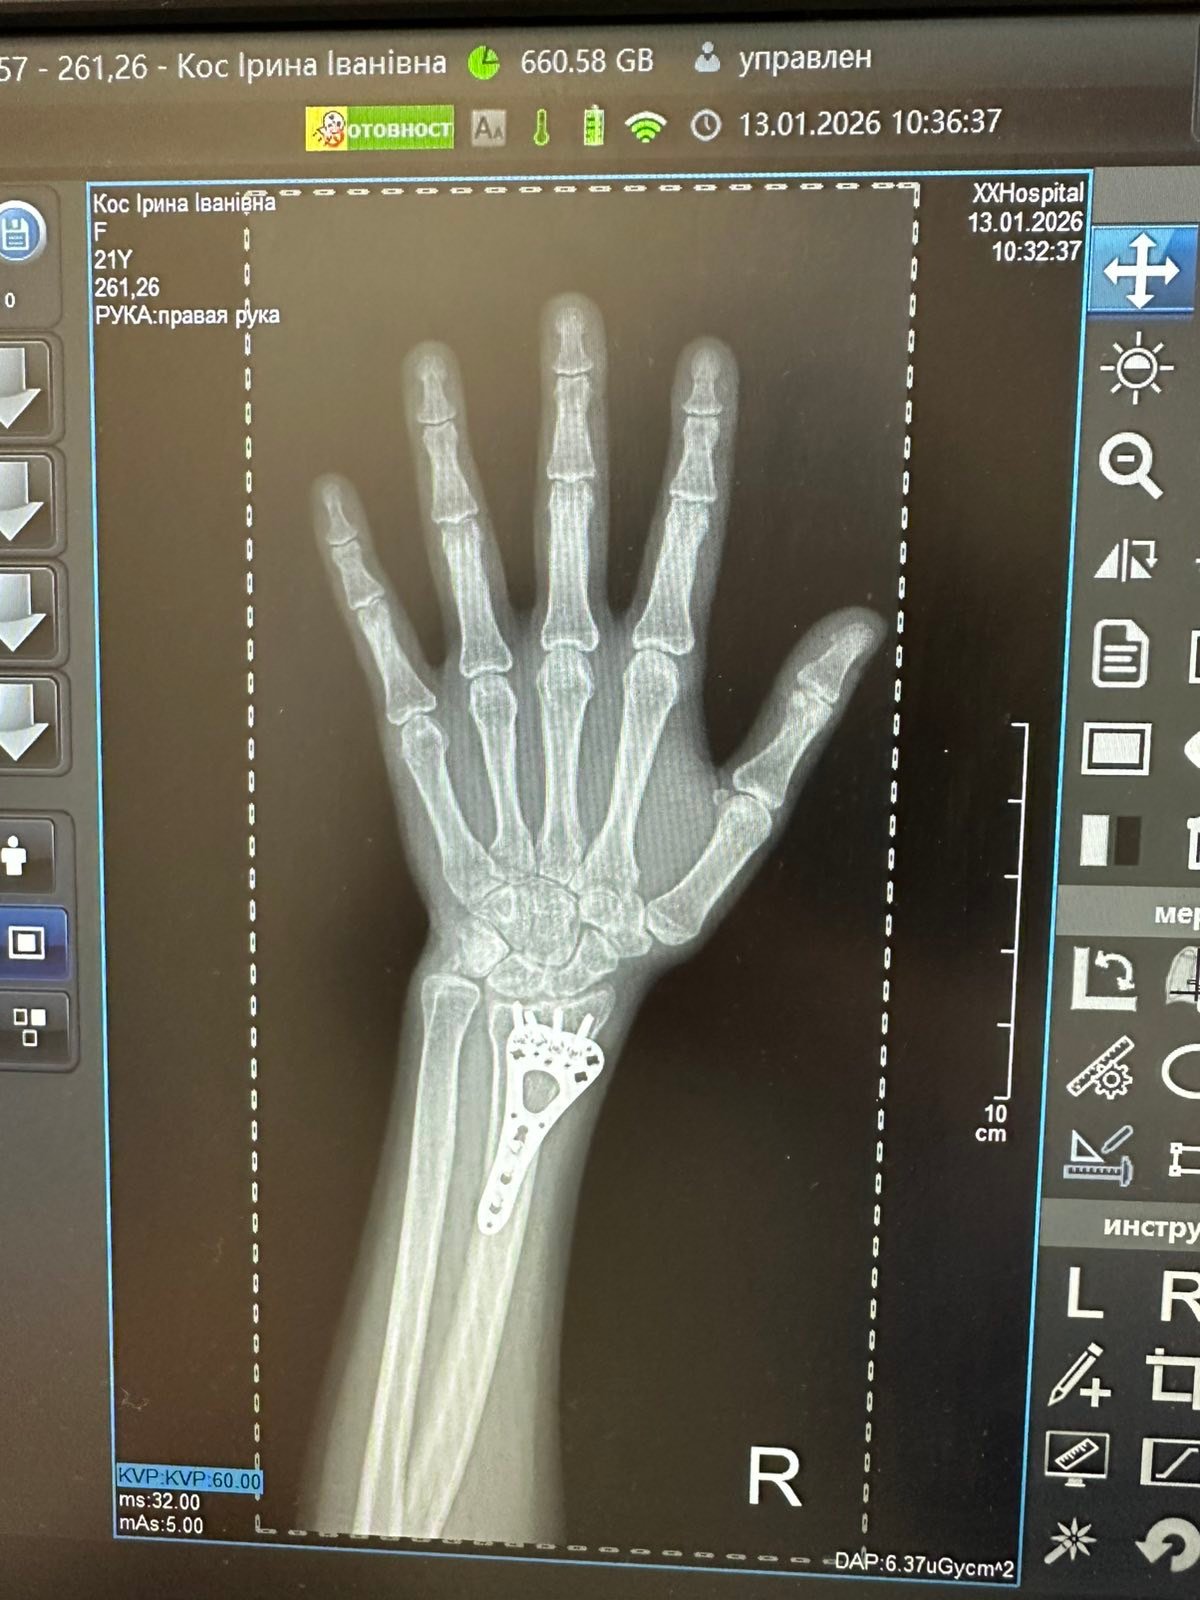

Під час оборони Бахмуту в районі населеного пункту Опитне після розриву танкового снаряду я отримав вогнепальне осколкове поранення правої кисті з наявністю стороннього тіла, вогнепальним пораненням 1 п’ястної кістки, дефектом м’яких тканин, дефектом кістки, вогнепальними осколковими пораненнями обох стегон.

По етапах трьохденної евакуації Дружківка–Дніпро–Львів прибув на лікування в хірургічне відділення ВП «Лікарня Святого Луки». Лікуючий лікар – Досяк Мирослав Ігорович.

Щодо перебігу лікування проведено оперативне втручання з видалення залишків снаряду, очищення вогнищ від сторонніх матеріалів і відмерлих тканин, накладання АЗР на кисть руки. Враховуючи вже чималий досвід лікування після поранень, хочу від себе особисто, а також від своїх побратимів, з якими разом прибув і проходив лікування, висловити щиру подяку лікуючому лікарю, Досяку Мирославу Ігоровичу, за високопрофесійну роботу, і на мою гордість, галицьку гостинність і розуміння.

Наслідки важкого поранення обмежили функції руки, та час вимагає ставати в стрій і міцно тримати зброю. Та й правиця у коваля повинна бути міцною і вправною. Після мого повторного звернення Мирослав Ігорович, відгукнувся, спланував і успішно провів кісткову аутопластику дефекту 1 п’ястної кістки МОС пластиною та теноліз розгиначів 1 пальця.

Міцність і функції правиці відновлено. Після реабілітації завдяки якісному лікуванню я знову зможу міцно тримати в руках і використовувати протитанкову зброю, та після нашої спільної Перемоги повернутися до свого ремесла.